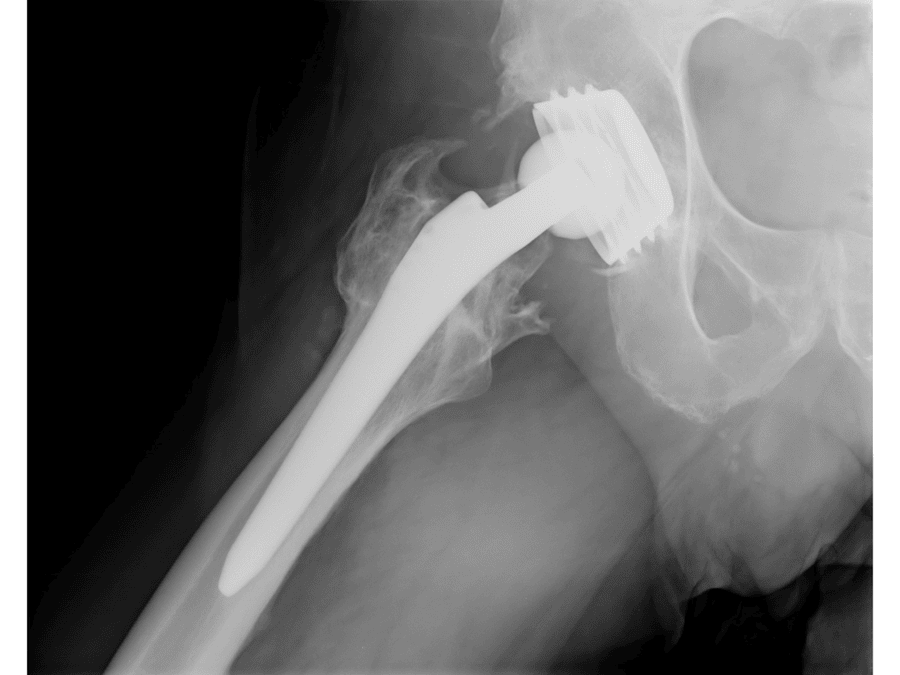

La rehabilitación postoperatoria es clave en cirugías de rodilla, hombro, columna, cadera y mano. Cada tipo de intervención requiere un plan específico que respete los tiempos de cicatrización y evolución del paciente.